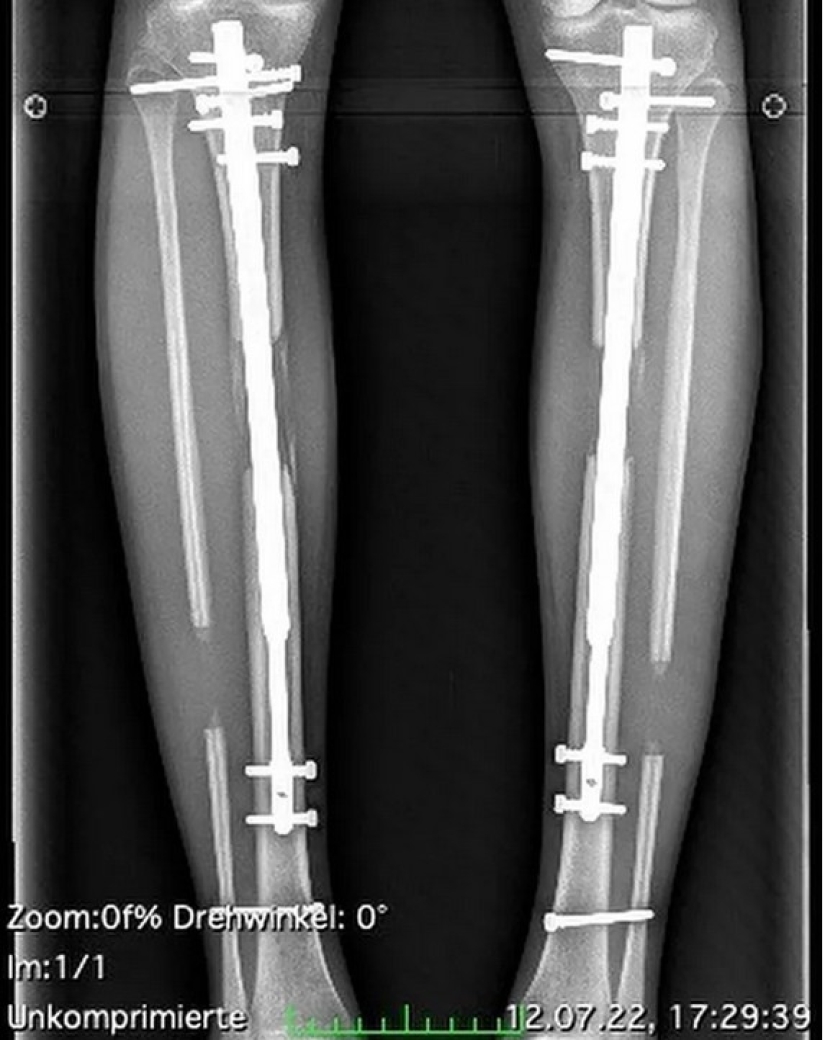

Leg lengthening surgery is a painful operation that unsettles a person for a long time. This is because the bones of the lower leg are broken, after which metal structures are inserted into them. And it's also very expensive. The model paid $160,000 (12.7 million rubles) for two surgeries and rehabilitation.

German Theresia Fischer gained fame thanks to her participation in the TV show "Germany's Next Top Model" in 2019. While working on the project, she repeatedly said that she was depressed by her short height of 170 cm and short legs. In 2019, Fischer underwent limb lengthening for the first time and became 8.5 cm taller. In 2022, she again went to the clinic and her legs were lengthened by another 5.5 cm.